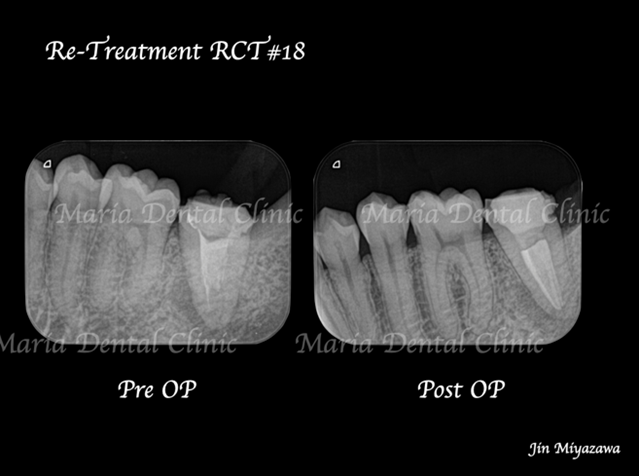

に対する、精密根管治療のアプローチ(再根管治療)_治療前後比較治療前のレントゲン画像.jpg)

に対する、精密根管治療のアプローチ(再根管治療)_治療前後比較治療後のレントゲン画像.jpg)

バイオセラミックにて根管充填を行いました。レントゲン写真からは根尖まで良好に隙間なく根管充填を行っていることが確認できます。

1回目の治療終了後、2週間後には違和感等は感じられないようにまで回復しました。